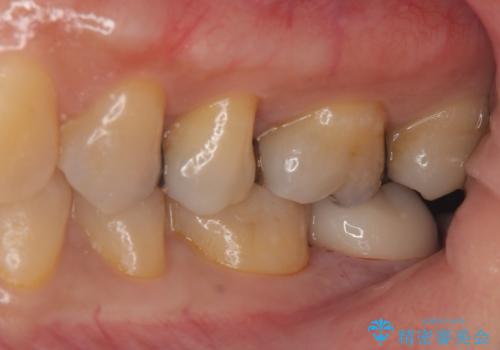

銀の詰め物が取れた。

- 銀の詰め物が取れたとのことで来院。

詰め物の下には虫歯がありました。

白い物で治療して欲しいとのことで、セラミックの詰め物だと詰め物の範囲が大きく、割れてしまう可能性があるので

ジルコニアクラウン(被せもの)で治療を行いました。

銀の詰め物はかなり昔に治療されたそうです。

銀の詰め物は虫歯の再発リスクが高く、歯に痛みが出てしまうと歯の神経の治療もしないとならなくなってしまいます。